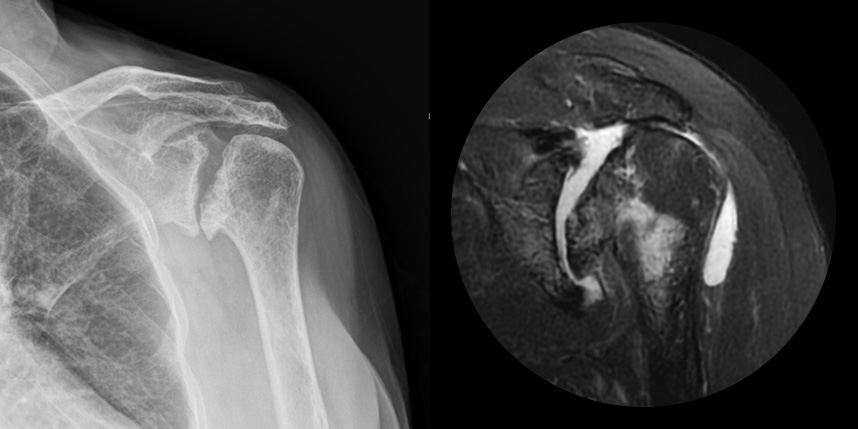

회전근개 파열의 크기가

매우 큰 경우

어깨 퇴행성은 많이 써서 닳고 노화에 따른 변화가 생긴 것으로, 말 그대로 어깨가 많이 사용되면서 연골이 닳아서

마모돼어 생기는 관절염입니다. 어깨 회전근개 관절병증 원인으로는 어깨 힘줄 파열을 방치했을 때 관절이 틀어진 상태에서 계속

사용하게 되면 관절이 많이 상해서 관절염까지 진행되며, 이런 경우 회전근개파열의 결과로 생긴 관절병이라고 합니다.